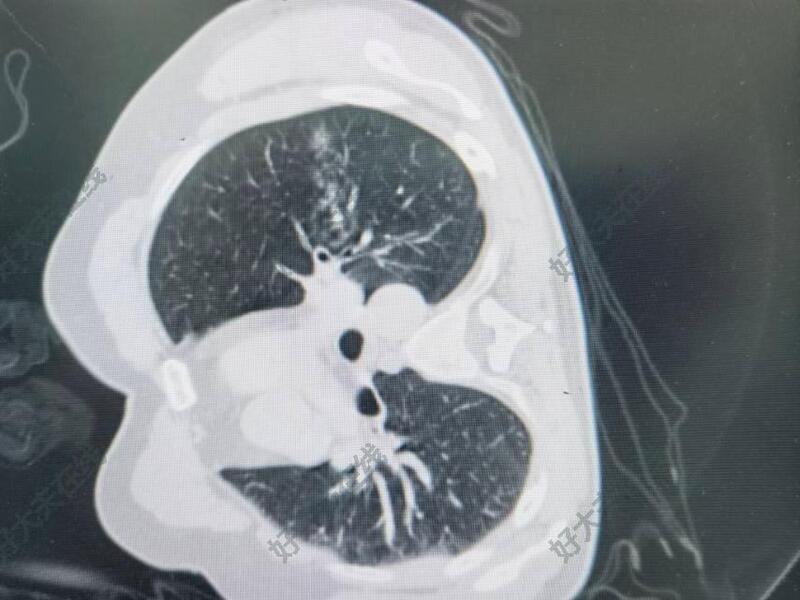

治疗后

- 治疗后即刻

患者顺利完成消融治疗,治疗后消融范围确切,充分覆盖肿瘤。